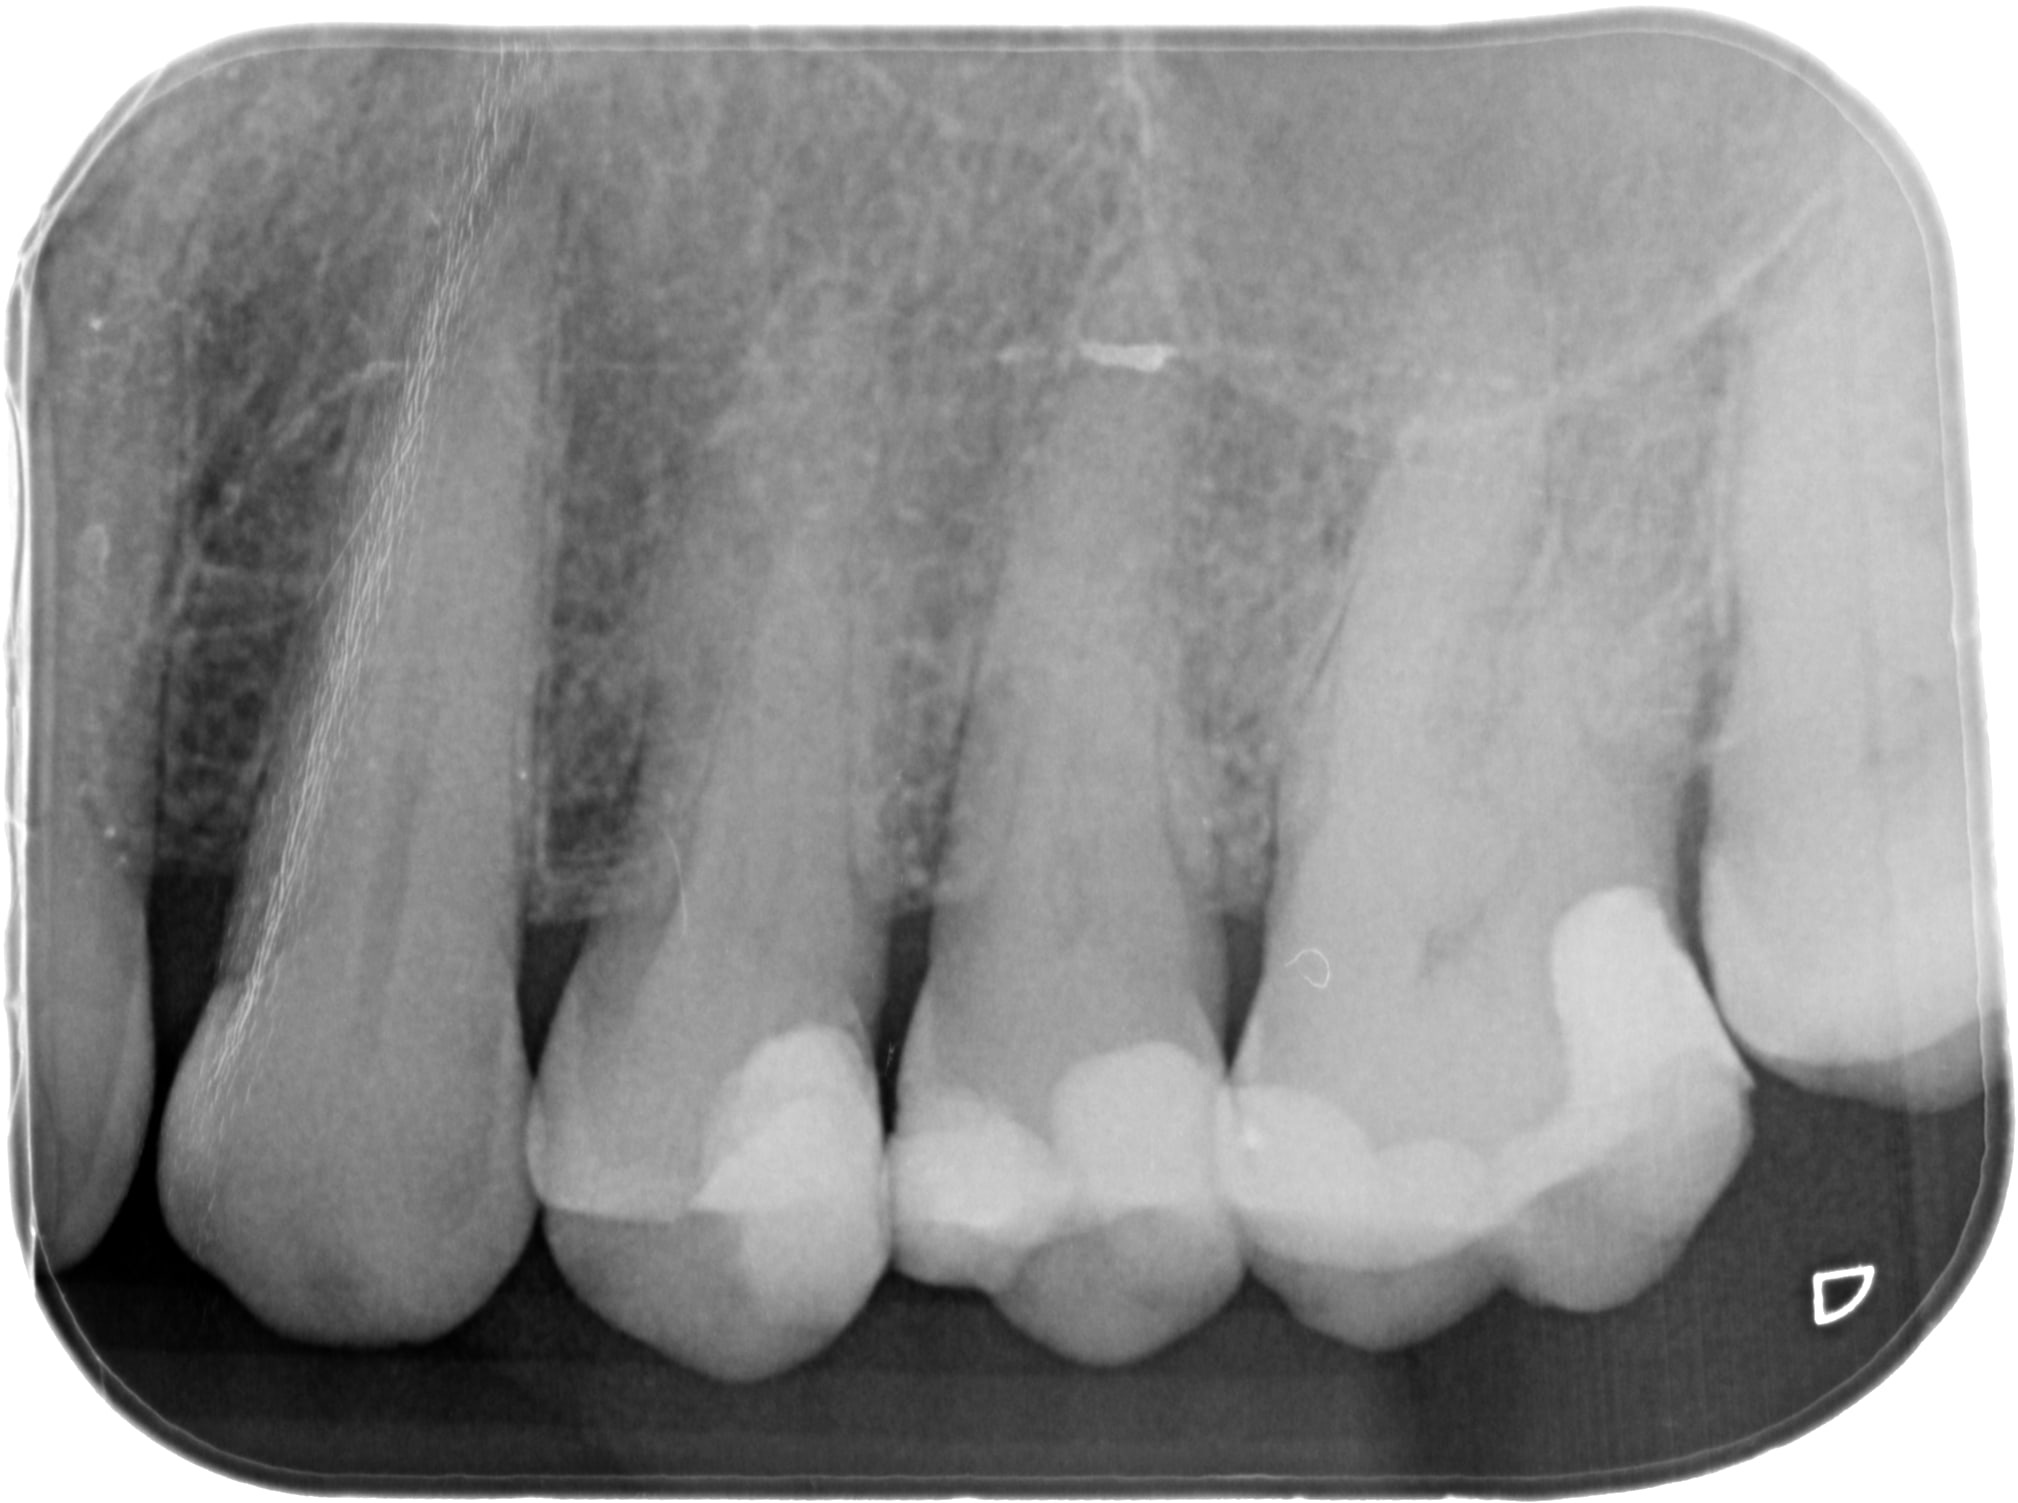

Compos de 1997..... 20 ans et un petit rafistolage cette semaine sur la 25.

Ça aurait Ă©tĂ© fait ces 5 derniĂšres annĂ©es je sais pas si j'aurais pas proposĂ© la coiffe..... Ă  croire que moi aussi je me laisse gagner par la lassitude de faire des soins de qualitĂ© pour des clopinettes.... et que bientĂŽt je saurai plus les faire :0(